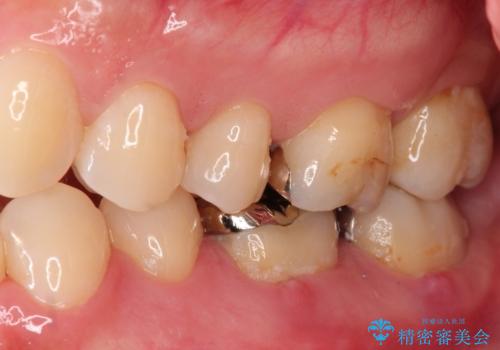

- 噛んだ時の痛みを主訴に当院受診されました。

根管治療を行なったのち、症状改善を認めオールセラミッククラウンにて修復治療を行なっております。

┌7は今回の治療後打診(-)、正常歯髄へ診断のもと経過観察を行なっております。